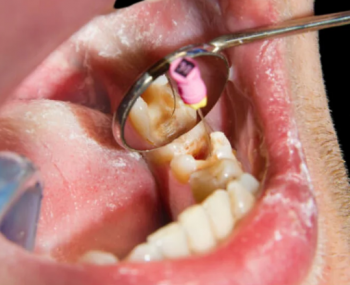

We see this too often in our clinic. Children from high-stress or separated families sometimes present with more cavities and gingivitis. It’s not just about sugar; it’s about sadness. When the structure of "goodnight, brush your teeth" crumbles, the consequences are more than just dental.